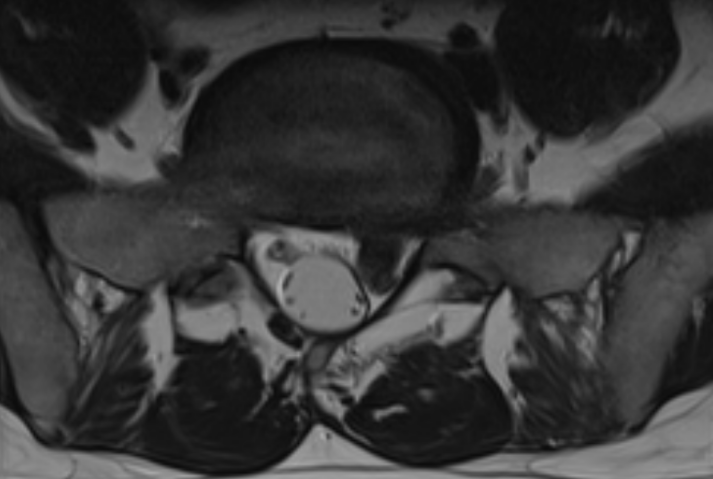

Disc protrusion - Left L5-S1